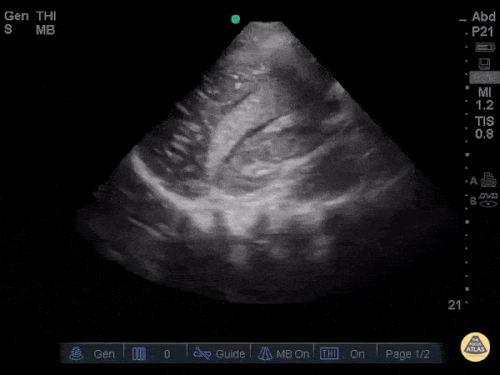

FAST: Morrison Alanı ve Normal FAST Görüntüleri

Normal FAST – Sol Üst Kadran (LUQ)

Normal FAST – Pelvis – Transvers

Normal FAST – Pelvis – Sagittal